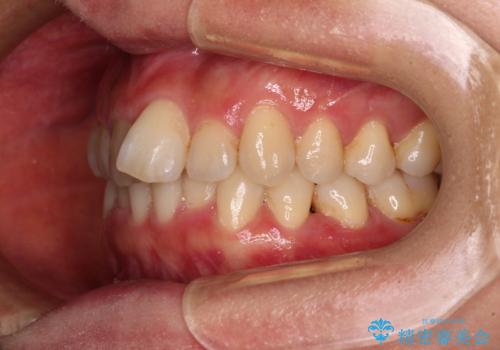

- 上下前歯のデコボコを気にして来院された患者様です。

叢生は軽度で、ワイヤー矯正でもマウスピース矯正でも対応可能な歯列でした。

僅か1年間できれいに歯列を整えることができ、患者様には大変満足していただきました。